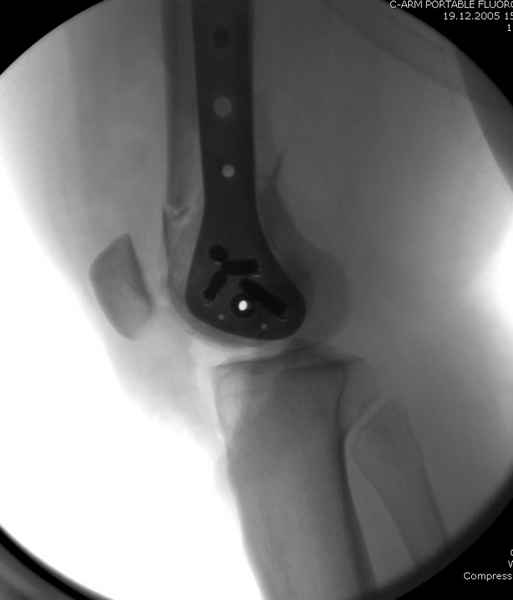

При наличии различных имплантов, любые варианты: слева (полу) открытым - мининвазивным, а справа закрытым интрамедуллярным методом, его считаем более чем приемлемым для фиксации данных переломов.

Проксимальная и дистальная блокировка, независимо от техники введения штифта, ретроградно или антеградно, гарантирует сращение сегментарных переломов бедра без укорочения. Штифты диаметром 12 мм с блокировкой сверху и вниз двумя шурупами выдерживают вес 75 кг больного, что позволяет раннюю профилактику контрактур.

Из-за вариабельности установки дистальных шурупов и возможности перкутанного введения проксимально предпочитаем DePuy Polyax, хотя на сегодняшнем маркете множеств вариантов фиксации дистального бедра перкутанном методом.